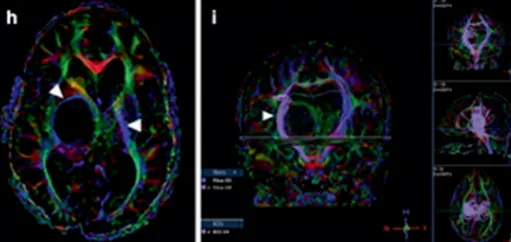

由于症状轻微而手术风险过高,术后可能较现状更差,医生评估认为不具备手术指征。然而肿瘤持续生长并形成多个小囊肿。同侧内囊(负责肢体运动功能)向前外侧移位,导致患儿从左上肢震颤进展为急性偏瘫。

马修首先接受神经导航和超声引导下活检,病理证实为WHO I级毛细胞星形细胞瘤。为治疗多发性囊肿,就诊于INC鲁特卡教授后植入Ommaya囊,并在超声引导下将导管置入肿瘤囊性成分。MRI复查显示囊性占位解除,脑室形态逐渐恢复正常。

4个月后偏瘫症状未改善,鲁特卡教授又为其行经胼胝体半球间入路肿瘤切除术,成功切除肿瘤。术后患儿偏瘫症状改善,生长发育和智力发育均恢复正常水平。